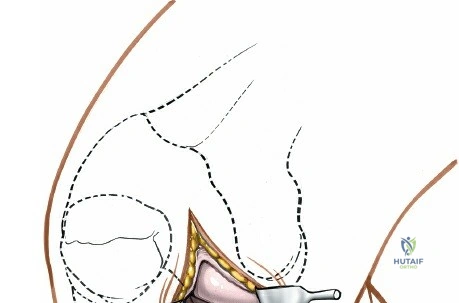

Open Medial Meniscectomy – The Specific Approach

The open medial meniscectomy, once the standard, is now reserved for scenarios where arthroscopy is unavailable, technically infeasible (e.g., severe arthrofibrosis, large foreign bodies, or specific revision surgeries), or for very large, difficult-to-manage loose bodies. The seed content heavily focuses on this approach.

Landmarks and Incision:

- Landmarks: Palpate the medial joint line, medial epicondyle of the femur, and medial tibial plateau. The saphenous vein and nerve courses superficial and posterior to the medial femoral condyle, requiring careful attention.

- Incision Options (as per seed content):

- Transverse Skin Incision: "over the joint line; although this limits the view of the knee, it provides better access to the meniscus itself." This may be suitable for isolated, easily accessible mid-body tears.

- Longitudinal or Oblique Incisions: "offer a better view of such other intra-articular structures as the cruciate ligaments." These incisions provide broader exposure and are generally preferred for better visualization of the entire meniscus and other intra-articular structures. A paramedial, slightly curved longitudinal incision, approximately 5-7 cm in length, centered over the joint line, is a common choice. It extends from just above the joint line distally to just below.

- The choice of incision depends on surgeon preference and the specific pathology being addressed.

Exposure of the Meniscus:

- Retractors are carefully placed to expose the medial tibiofemoral compartment. Self-retaining retractors may be used, but care must be taken to protect the articular cartilage.

- To improve visualization, the knee is brought into hyperflexion (as per seed content, "beyond a right angle"). This maneuver, combined with external rotation of the tibia and a valgus stress applied to the knee, widens the medial compartment. This allows for improved access to the posterior horn of the medial meniscus.